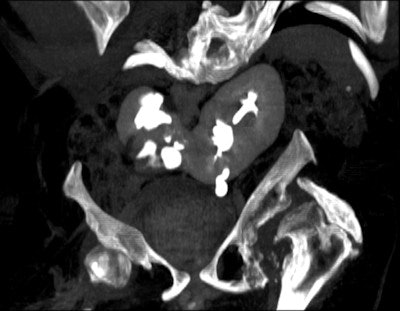

An 18-year-old female with "after-party amnesia" presented with severe stomach pain and bruises to the head. An investigation showed vaginal bleeding was from the bladder. Full-scale emergency room investigation showed severe left kidney fracture and contusion, but intact vessels and ureter. Three-month follow-up renography shows 28% kidney function on left side as the only sequelae. Image courtesy of Dr. Vibeke Logager.